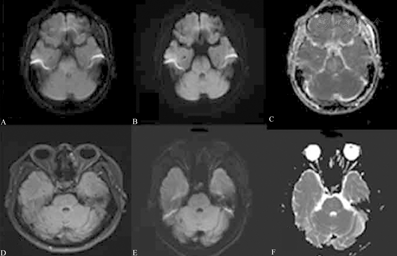

病例1:男性,37岁,因"头晕伴复视3 d"入院,既往有高血压史5年余,最高170/100 mmHg(1 mmHg=0.133 kPa),未规律治疗。有烟酒史20年。入院查体:血压200/130 mmHg,神志清楚,语言流利,双侧瞳孔等大等圆,直径2.5 mm,对光反射灵敏,双眼左视时可见水平及向上旋转性粗大震颤,左侧上睑稍无力,左眼内收受限1 mm,左眼外展受限1 mm,右眼外展受限1 mm,四肢肌力正常,脑膜刺激征阴性,病理反射未引出。常规血液化验和脑脊液检查均未见异常。头颅MRI示脑干右侧信号异常,T1等信号,T2高信号,液体衰减反转恢复序列(fluid attenuated inversion recovery, FLAIR)为高信号,弥散加权成像(diffusion-weighted imaging, DWI)为低信号,表观弥散系数图(apparent diffusion coefficient, ADC)为稍高信号(图1)。考虑恶性高血压引起PRES,给予控制血压、营养神经、改善循环等治疗后,血压控制良好,头晕和复视症状好转出院。1个月后复查头颅MRI示病灶完全消失。

患者男性,37岁,因"头晕伴复视3 d"入院,治疗前头颅MRI示脑干右侧散在小斑片状异常信号,液体衰减反转恢复序列呈高信号(A),弥散加权成像呈低信号(B),表观弥散系数图呈稍高信号(C);出院1个月后复查MRI示病灶完全消失(D~F)